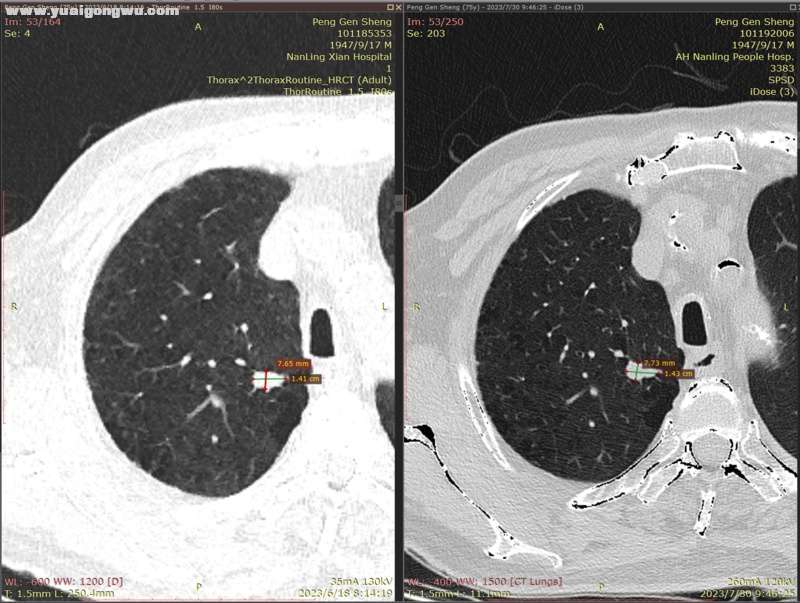

6月3日~7月29日,单用安罗替尼12mg(3周期),6月18日CT显示左肺主病灶稍缩(主病灶62mmx57mm);因近期有一点点吸不上气的感觉(吸氧后有缓解,其他身体体征正常,体感良好),7月30日CT显示左肺主病灶稍增大(主病灶68mmx62mm)。- L* L' w9 C: J7 b

影像科医生将7月30日的胸部CT,和6月18日的胸部CT电子影像对比分析如下:

: v& _. J  {' _( E1 `) |4 A: L* ^         1、左肺上叶主病灶(肿块),7月30日复查较2023.6.18略增大,如图红圈所示,局部边缘饱满(图1);: O% K* B! J8 F9 Q9 t8 j3 d

2、右肺多发小结节,前面两枚之前重点关注的结节(有时变大有时变小),这次复查略微变小(图2~5;+ }% G% E$ F0 e  U; {- |' V' B

* R5 w. e) k/ [9 Y( L' s' h* x* n7 d        以下为近两次CT影像的对比分析。7 Z8 B" @7 n7 B# ?+ K" ?( E( {) v